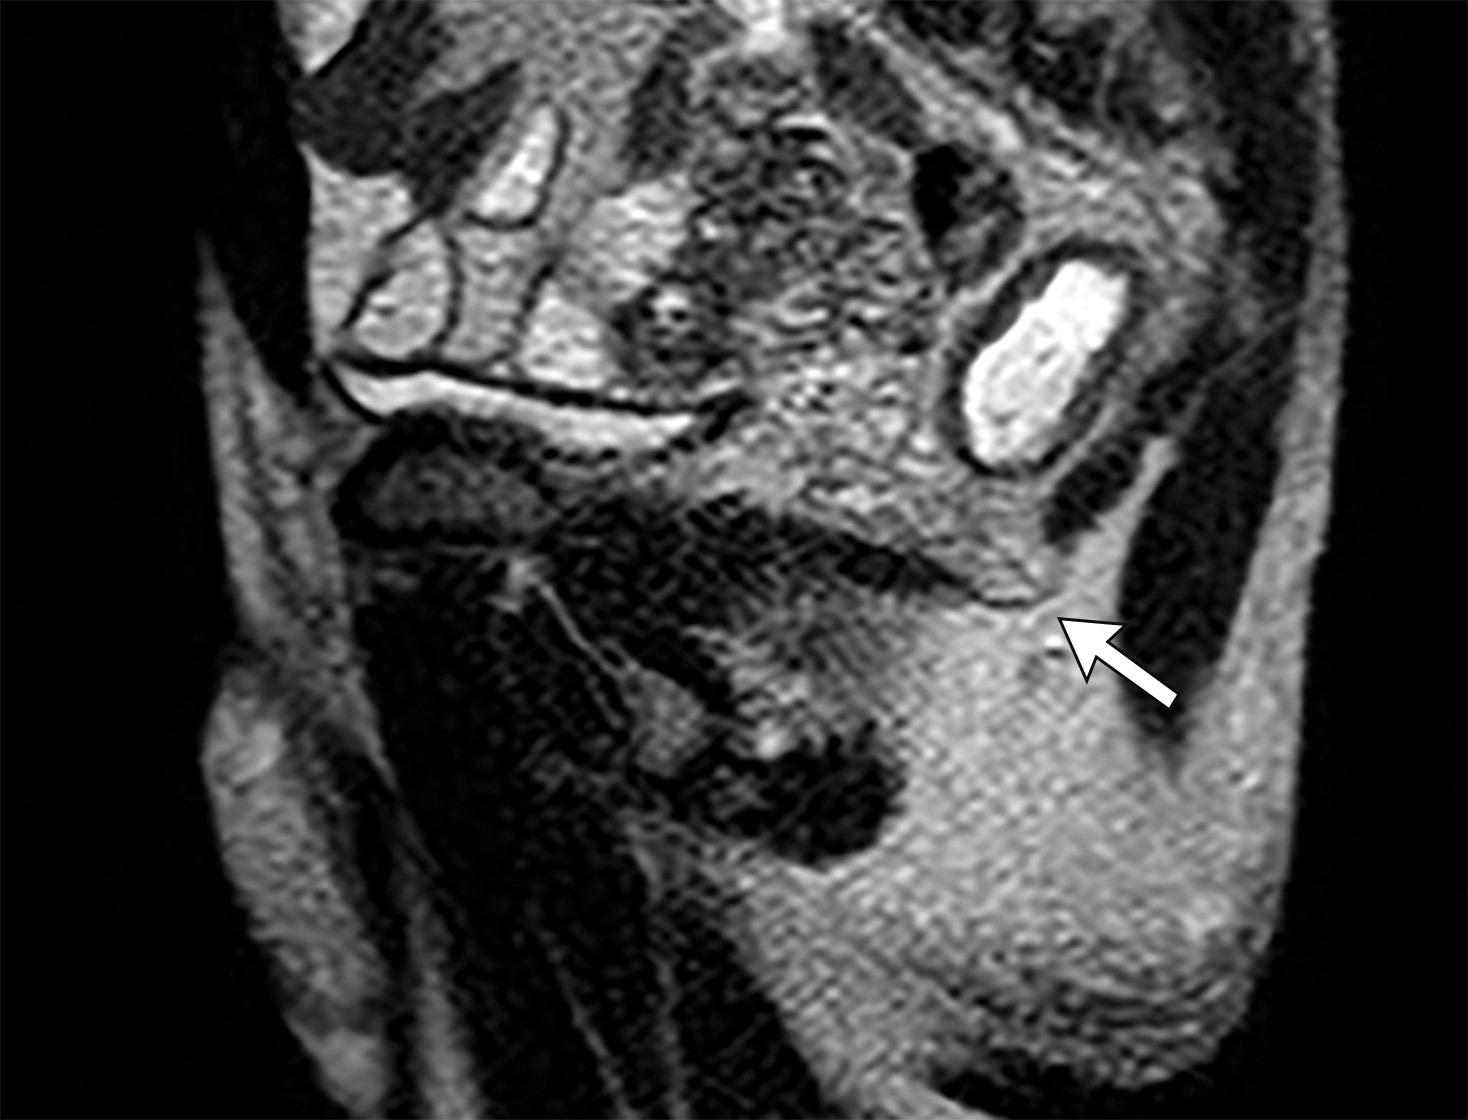

1327c40cd0748e6d87b4cfea2fce8541.jpeg5e035c7e4059e08fb1d03d282633f38e.jpeg髂尾肌的不同形态。

(上图)右侧髂尾肌萎缩(上图白色长箭头),复发性直肠腺癌(上图黑色字母A),(下图)另一个患者,双侧髂尾肌增厚(下图黑色短箭头)。